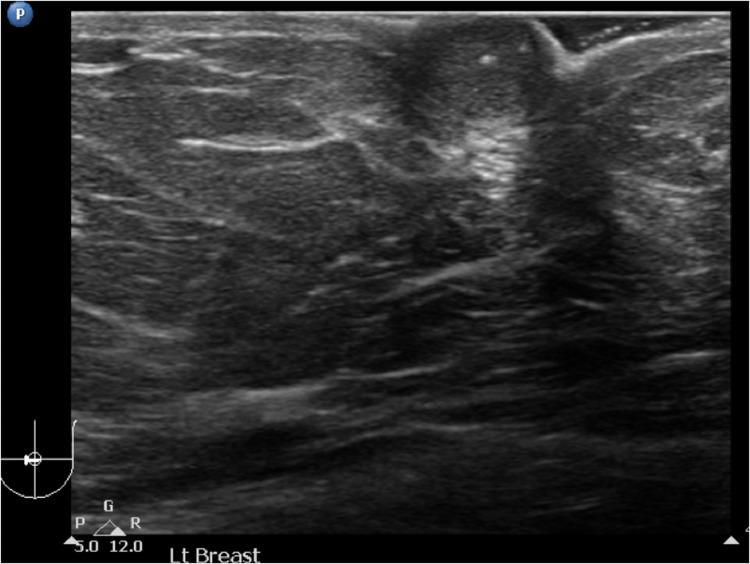

A 62-year-old woman was presented with blood stained nipple discharge for many years. Mammograms and ultrasound study revealed a prominent left nipple, increase in nipple vascularity and nipple calcifications. Ductogram revealed an obstruction at the proximal part of the discharging duct. Surgical excision of the nipple demonstrated encapsulated papillary carcinoma. The excision margins appeared to be clear, but tumor tissue was found within 1 mm from the deep margin. Ultra-filtered sulfur colloid sentinel node examination was negative. Thus, simple left mastectomy was performed. The specimen was confirmed as ductal carcinoma in situ of the left breast.